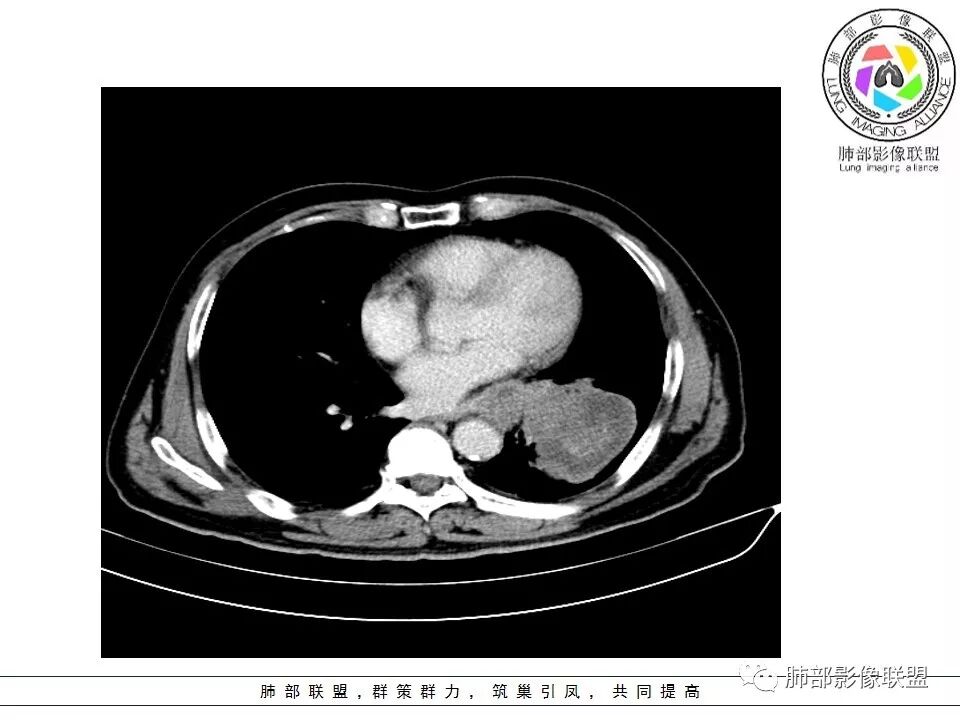

1.左肺下叶近肺门区肿块,肿块外围大,内带小,提示外围向中央生长,符合周围型SCLC沿支气管方向生长。

2.病灶边缘光滑,未见明显分叶、毛刺,符合神经内分泌癌、癌肉瘤及间叶来源肿瘤。

3.病灶内密度偏低,穿行血管未见明显异常,轻度不均匀强化,为乏血供病灶。病灶内可疑坏死区,未见空洞;乏血供符合SCLC,但坏死区不符合。

4.病灶区支气管以受压推移为主,管腔不规则,腔内通而不畅,提示病灶粘膜下为主,符合SCLC迁徙蔓延或间叶来源肿瘤。

5.病灶内有血管走行,血管局部受压,但是强化考虑为乏血供,提示病灶内肺动脉并不是供血血管,只是病灶侵袭性强把血管包埋而已,为血管包埋征;血流面光滑,血管包埋符合SCLC。

6.左肺门淋巴结肿大,与病灶局部融合分界不清,呈冰冻肺门;而纵隔内未见肿大淋巴结,冰冻肺门符合SCLC,但是病灶主体那么大,纵隔内没有明显肿大淋巴结,不是很符合SCLC娘小崽大的特点。

7.未见明显阻塞性炎症及阻塞性肺不张,更加提示病灶从外围向中央侵犯,符合SCLC罕见阻塞性肺不张。

综上,影像学该病例符合肺内恶性,来源考虑神经内分泌癌、癌肉瘤或间叶来源肿瘤。老年男性,较大病灶伴有坏死,所以有群友考虑鳞癌、大细胞癌、癌肉瘤和肉瘤,但是鳞癌、癌肉瘤坏死常常合并空洞,而且像大细胞癌、癌肉瘤和肉瘤破坏力强,容易破坏血管;肉瘤一般不会引起肺门及纵隔的淋巴结肿大,所以肺门淋巴结肿大也不是很支持肉瘤。该病例部分征象支持小细胞癌(SCLC)的诊断。同病异影、异影同病都需要我们仔细甄别。